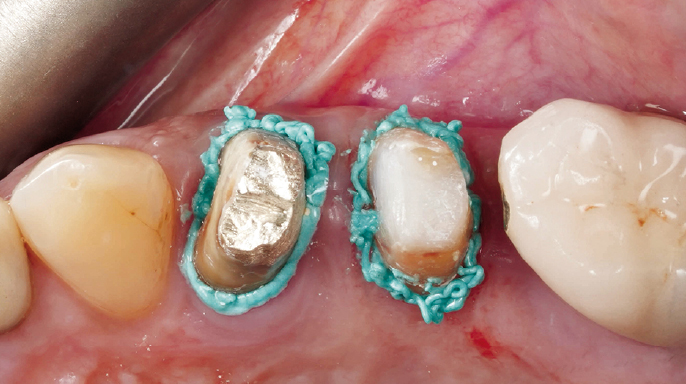

EndodonciePacient se dostavil do ordinace, nespokojený s estetickým výsledkem korunek na zubech 24 a 25. Klinické vyšetření prokázalo nevyhovující marginální uzávěr u obou korunek, a proto bylo indikováno zhotovení nových protetických rekonstrukcí.

Termín chirurgická endodoncie označuje obor stomatologie, který se zabývá diagnostikou a léčbou lézí endodontického původu, jež nedostatečně reagují na konvenční endodontické ošetření nebo je nelze konvenční cestou ošetřit vůbec.¹ Cílem chirurgické endodoncie je dosažení trojrozměrného vyčištění, opracování a zaplnění apikální části kořenového kanálkového systému, která není přístupná běžným ortográdním přístupem dřeňovou dutinou, ale pouze po odklopení chirurgického laloku (obr. 1.1).